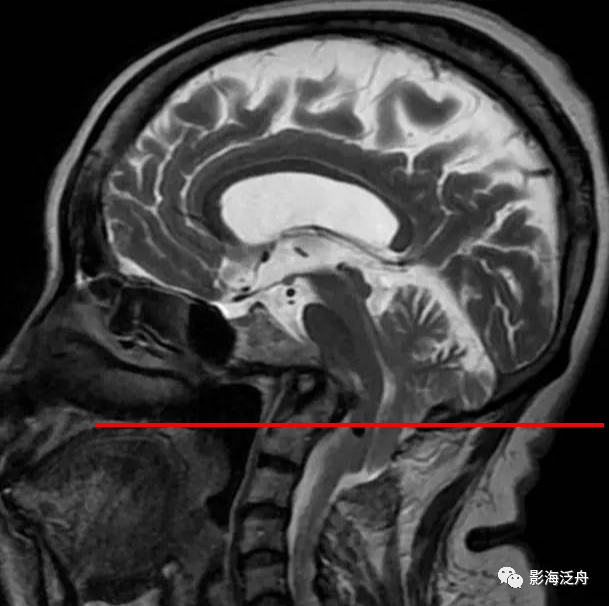

乳腺癌

术后患者,枢椎骨质信号异常,随访证实为骨转移。随着肿瘤患者越来越多,行颅脑MR检查排除脑转移的检查也逐渐增多,不要只顾着在脑子里面找转移灶,周围的结构也应该观察一下。

矢状位上另一个需要观察的就是齿状突的高度,异常增高往往是颅底凹陷症导致的(红线为钱氏线)。